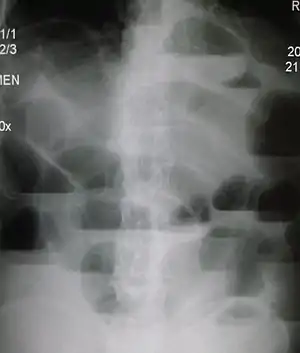

Radiological signs of bowel obstruction include bowel distension and the presence of multiple (more than six) gas-fluid levels on supine and erect abdominal radiographs. Ultrasounds may be as useful as CT scanning to make the diagnosis.[17]

Contrast enema or small bowel series or CT scan can be used to define the level of obstruction, whether the obstruction is partial or complete, and to help define the cause of the obstruction. The appearance of water-soluble contrast in the cecum on an abdominal radiograph within 24 hours of it being given by mouth predicts resolution of an adhesive small bowel obstruction with sensitivity of 97% and specificity of 96%.[18]